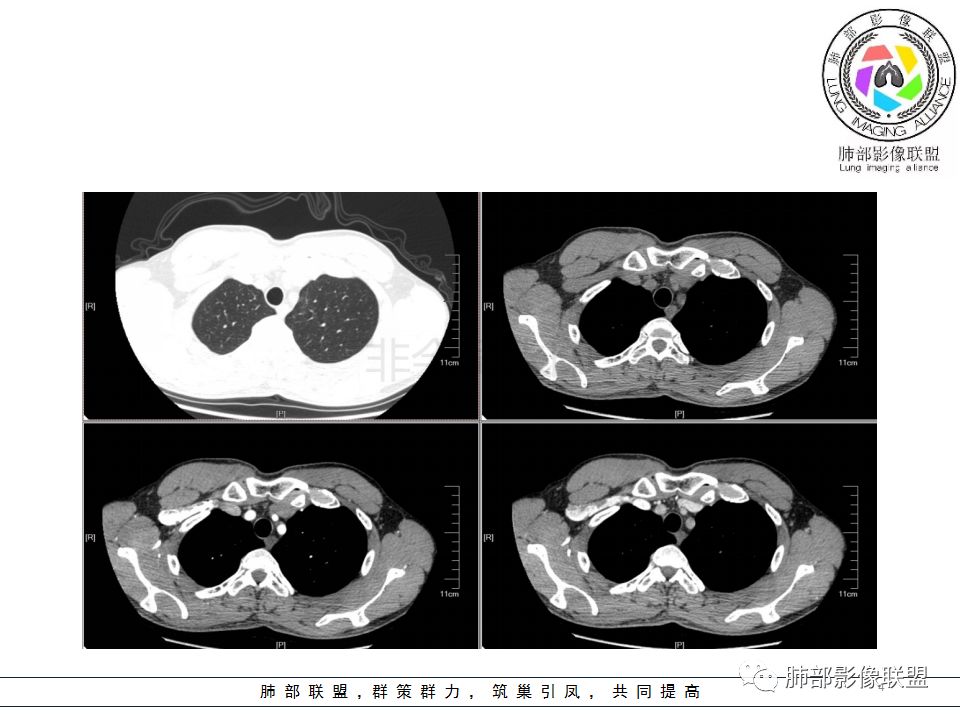

wonderful:答案

南边:

支气管树爬行征这个观点是袁怀平老师提出来的。当时提出了一个观点,就是说支气管是通畅的。

现在就是支气管树爬行征的认定问题,就是关于支气管通与不通?如果堵塞,在哪个区域堵塞?

支气管树爬行征就是肉芽肿性病变,不过它是沿着支气管周围间质往里面走的。我们以前认定支气管要通畅的,但是我们读了隐球菌发现,包括肺炎性肺癌,你就发现外围的病变往内带进展,可以支气管堵塞,例如隐球菌有个特点非常明显的,一个大片状影,支气管在中近端堵塞。我们反推过来,结核也可以这样变化;支气管爬行征原来是要求支气管通畅,改良为支气管可以通畅,也可以在中间堵塞。

该如何判断支气管树爬行征,还需要大宗数据进行观察总结。

支气管树爬行征:肺内结核性肉芽肿的特征性CT征象之一